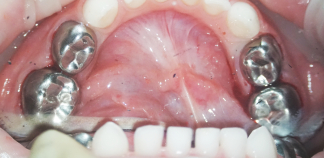

До лечения

Жалобы на зубную боль от сладкого и ночью.

Пациенту 4 года.

Как лечили

Лечение кариеса под наркозом. Перед лечением проведена профессиональная гигиена полости рта. После лечения кариеса зубов и фиксация металлических коронок на жевательные зубы.

Лечение проведено за один визит.